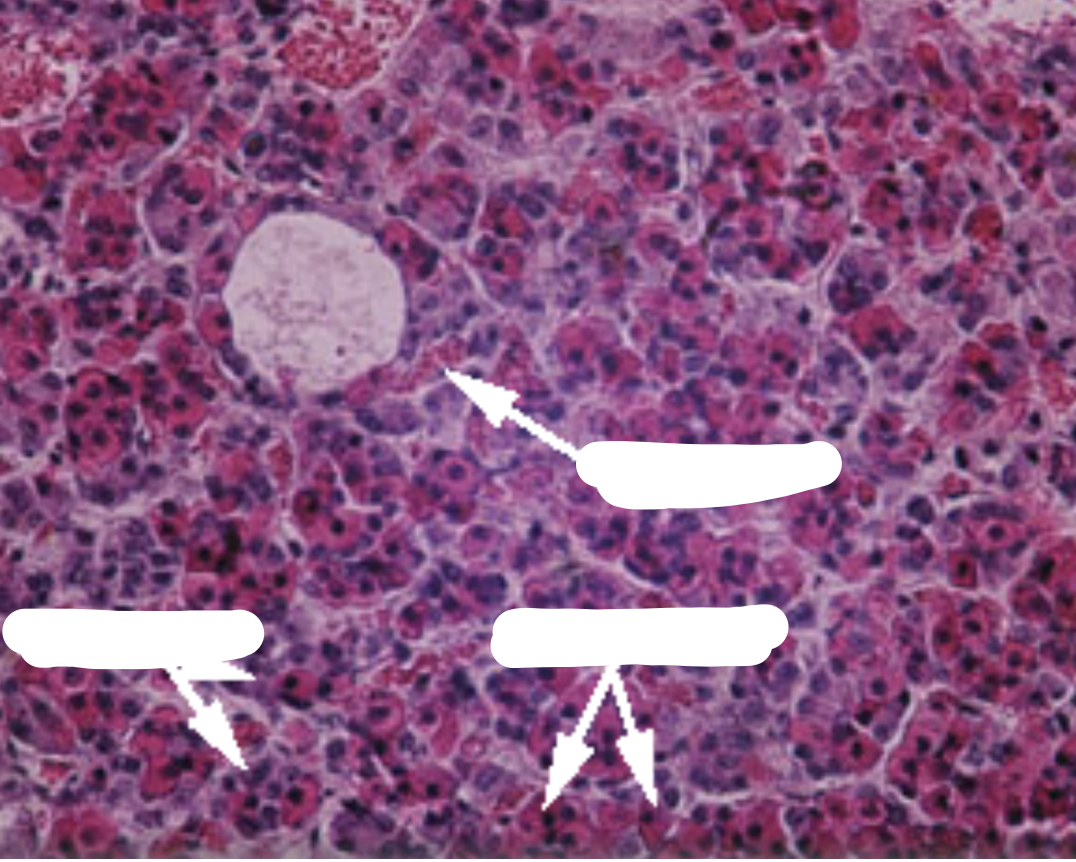

What gland is shown here

Parathyroid gland

How are hormones stored in a thyroid gland?

Hormones are stored in cavities, surrounded by secretory cells. These make up a follicle. Within the cavity of the follicle, the hormone is bound to a glycoprotein and is called as colloid. During secretion the hormone is re-absorbed from the cavity, and then released into the surrounding interstitial spaces.

Fill in the blanks

1 = Thyroid follicle: follicular cells + colloid

Thyroid cell- produce thyroid hormones & their surface contains TSH receptors

2 = Follicular epithelial cells

3 = Parafollicular (C cells)- secrete calcitonin - takes calcium & puts it back into the blood

NB. parafollicular cells arise, separately from the thyroid and migrate into it during development of the embryo

PARAFOLICULAR CELLS are secreted from the THYROID GLAND (not the parathyroid gland, this secretes parathyroid hormones which increase calcium levels)

What type of epithelium do you see lining the follicle?

Simple, non-stratified, cuboidal epithelial cell (found in all endocrine glands)

What hormone do the C cells and the thyroid gland secrete?

C cells= calcitonin

Thyroid gland = T3&T4